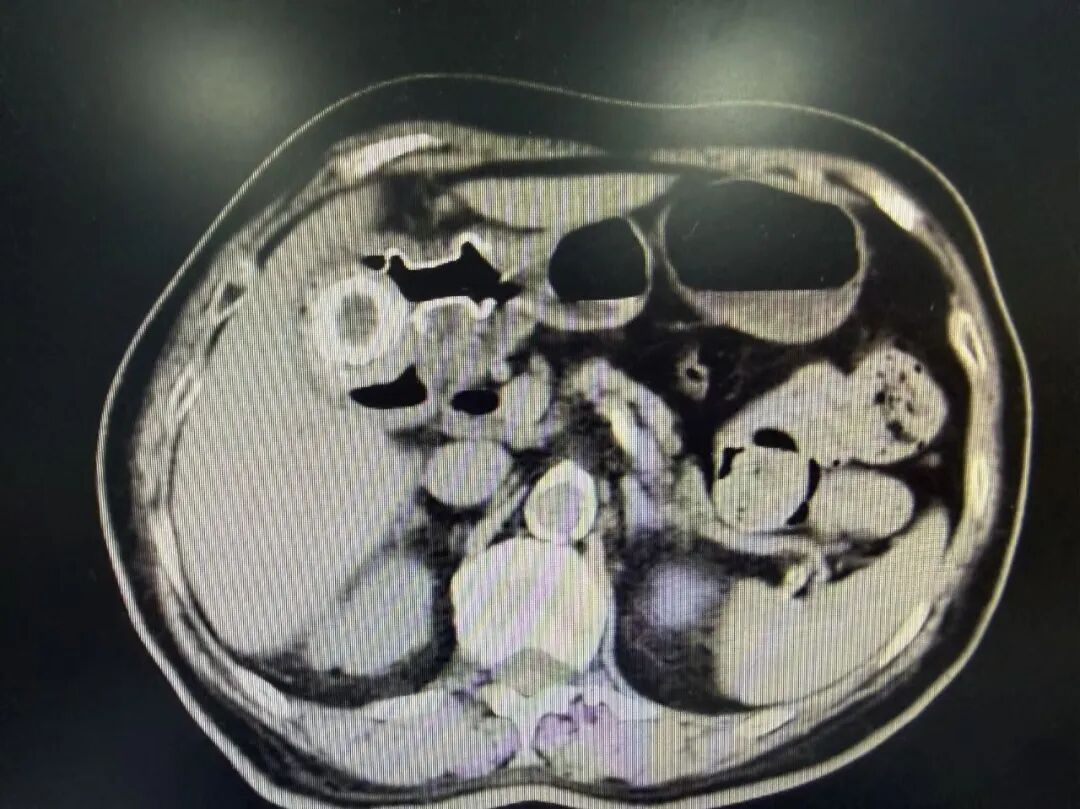

患者为82岁女性,深受胆囊结石病史折磨30年,此次因胆囊巨大结石合并急性胆囊炎入院,且患有高血压、冠心病、糖尿病等多种基础疾病,无法耐受常规外科手术。面对治疗困境,医院肝胆胰腺内科多学科团队经过综合评估,决定为其施行创伤更小、恢复更快的超声内镜介入治疗方案。

第二阶段:经吻合口通道行液电激光碎石术

支架置入约2周后,手术团队将液电激光碎石探头经已建立的通道精准导入,对患者胆囊内一枚直径达4厘米的巨大坚韧结石进行碎裂。在李金厚的精细操作及内镜中心护理团队的默契协作下,最终将结石碎裂成可排出的细小颗粒并取出体外,彻底解除了病灶。患者术后恢复顺利,已康复出院。